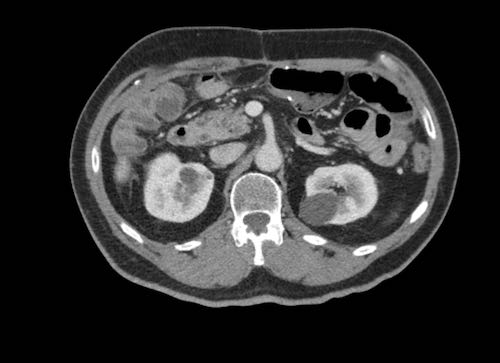

Cuộn xem ảnh CT

Ca lâm sàng 1

Cuộn qua các lát cắt.

Bạn có thể phát hiện tất cả các tổn thương cấy ghép phúc mạc không?

Bệnh nhân này đã được phẫu thuật và toàn bộ phúc mạc được ghi nhận phủ kín bởi các tổn thương u dạng kê.